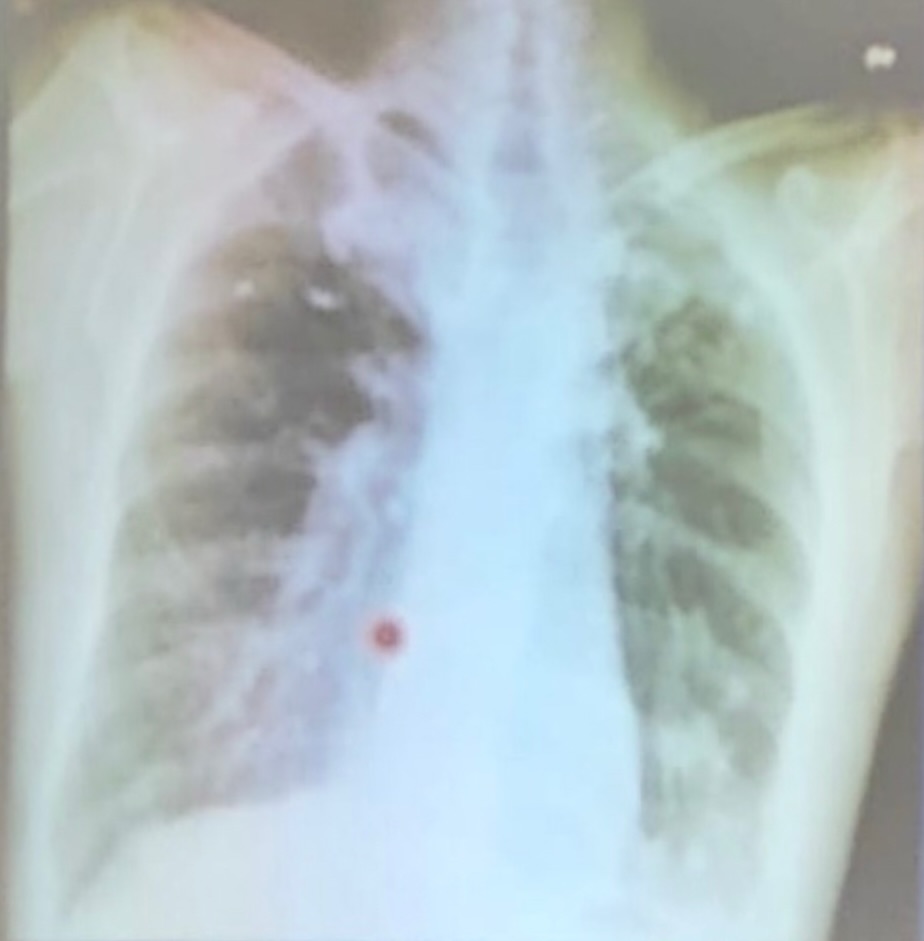

tuberculosis